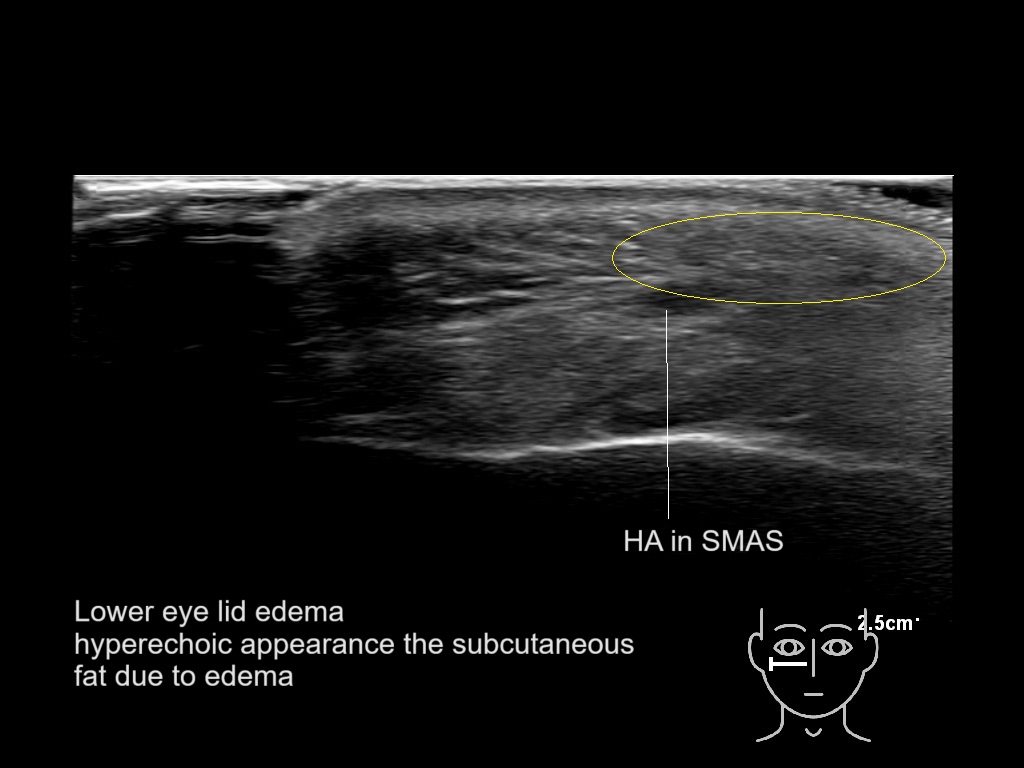

With ultrasound signs of inflammation can be visualized. Edema can be seen as a hyperechoic appearance of the subcutaneous fat, sometimes separated by hypoechoic fluid filled area’s, known as cobblestone appearance. Increased vascularization (hypervascularity) can be seen on colour Doppler. An abscess will appear as a fluid collection appearing as an irregular hypoechoic area with heterogeneous internal echoes and a thickened wall. Posterior acoustic enhancement can be present, and there is vascularity around but not within the mass. Under ultrasound guidance, abscesses can be managed by needle aspirations (18G) under antibiotic cover.

Study the first image to recognize the different layers. If you are sure about the layers, swipe to the second image to view the answer (if applicable).